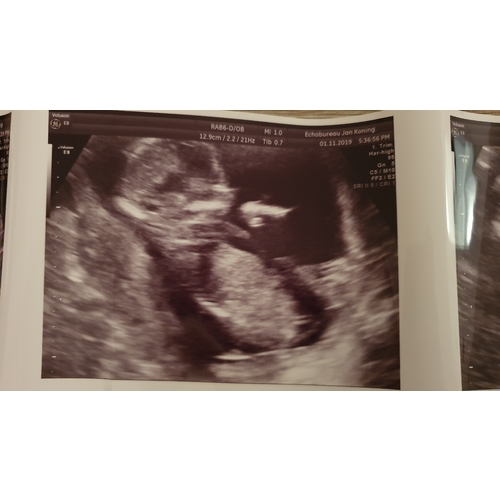

Bij de eerste had Jan Koning het goed. Bij de tweede met 14 en 1 weken geslachtsbepaling gehad. Nu met de 30 weken echo was het nogsteeds datzelfde geslacht. Ik geloof wel dat het soms toch niet kan kloppen, maar ken persoonlijk niemand die bij hem is geweest en waar het niet juist was

De streepjes lijken precies hetzelfde inderdaad! Bedankt dat je de echo liet zien!